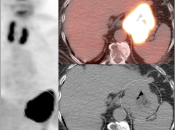

• Hiatal Hernia: Increased metabolic activity is frequently encountered within a hiatal hernia. Such uptake is nearly always physiologic or inflammatory. Malignancy, however, sometimes cannot be excluded and upper endoscopy may be required.